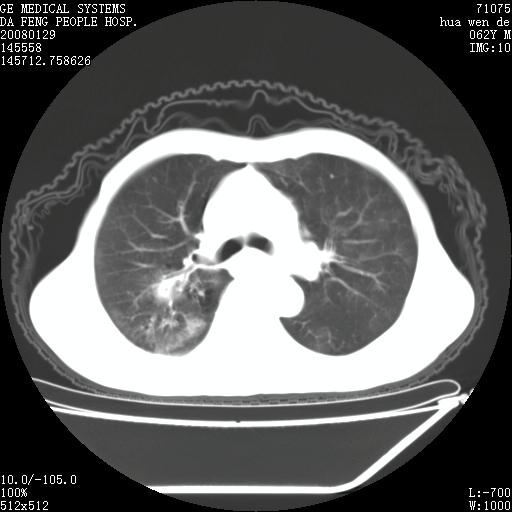

男性,67岁。作肺部检查时发现

右肺脓肿 胸腔胃

考虑1、右肺周围型肺癌可能性大。

2、贲门失迟缓症可能,建议钡餐检查。

考虑:胸腔胃并支气管瘘(并发肺炎,肺脓肿形成)。

理由:1、右上肺内病灶,空洞形成,有液平。

2、肺内多处炎症。

3、前段肺内炎症,支气管引流通畅,与肿块无关系。

1.整个食管扩张,未见明显占位性病变,贲门区亦未见明显占位病变,考虑:贲门失驰缓症;

2.右上肺病变边缘可见毛刺,囊壁厚度不均匀,周围境界较清楚,未见炎性渗出性影,右上肺外带可见片状影,边缘不清,考虑:肺癌伴空洞形成、右上肺炎。

食管全程扩张,壁均匀不厚,喷门失弛缓症

右上肺空洞可见液平,临近肺野磨玻璃密度,考虑1.结核2.脓肿